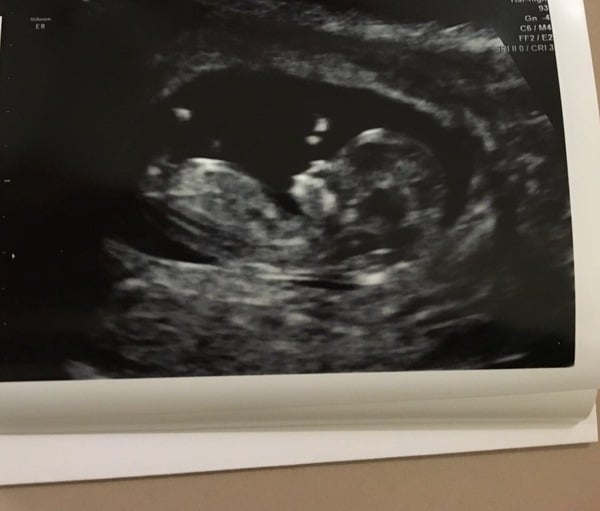

Dixie congrats on your scan, pleased they did manage to get the NT measurement. Bit concerned (as a wheelchair user) about the possible need to move around lots to try and get baby to move at hospital for scan... fingers crossed it'll be alright for me somehow. My 12 week scan is 2 weeks tomorrow at bang on 12 weeks, really looking forward to seeing baby again.